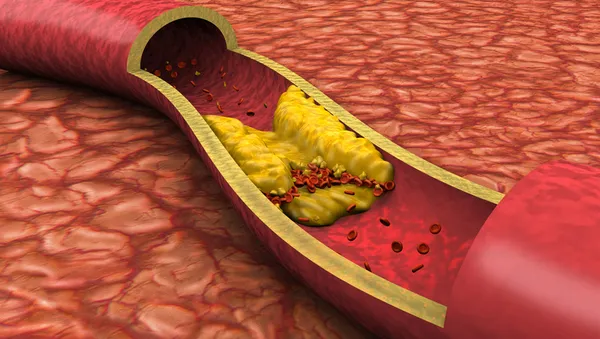

Ulusal Vasküler ve Endovasküler Cerrahi Derneği Başkanı Doç. Dr. Soner Yavaş ise kalp damar sisteminin hayat boyunca dinlenmeden çalışan sistem olduğunu vurguladı. "Kan basıncına karşı çalışıyor. Bunun için sürekli hastalıklara açık. Kalpten çıkan aort dediğimiz ana kanı taşıyan damar hayat boyunca yaklaşık 200 milyon litreye yakın kan geçiriyor içinden. Bütün organların ana dalları bu damardan çıkıyor. Bu damarda balonlaşma veya tıkayıcı hastalık görülebiliyor. En çok anevrizma görülüyor. En sık batın bölgesinde anevrizma gözükmekte. Yaş ile sıkıntı artmakta. Gençlerde de görülüyor. 65-74 yaş arasında 100 binde 55 görülme sıklığı var. Erkeklerde daha fazla tansiyon olması, tütün kullanımı, koah gibi hastalıklar da beyaz ırkta daha fazla görülmekte. Tanısı kolay aslında bu hastalıkların. Ne yazık ki toplumda bilinç oluşmamış durumda. Rutin kontrolde kolaylıkla saptanıyor. Tam bilinmediği için bazen çok gecikmiş hastalık olarak geliyor. En korktuğumuz damarın patlayarak gelmesi. Patlayarak gelen damarlarda ölüm oranı çok yüksek" diye konuştu.

Ulusal Vasküler ve Endovasküler Cerrahi Derneği Başkan Yardımcısı Prof. Dr. Nevzat Erdil, şah damarın beyni besleyen oksijen taşımasını sağlayan damar yapısı olduğunu hatırlattı. Bu damarda tıkanmaya bağlı insanlarda inme hastalığı olduğunu anlatan Prof. Dr. Erdil, ileri yaşa, sigara ve tansiyona bağlı bu hastalığın son dönemde gençlerde de rastlandığını söyledi.